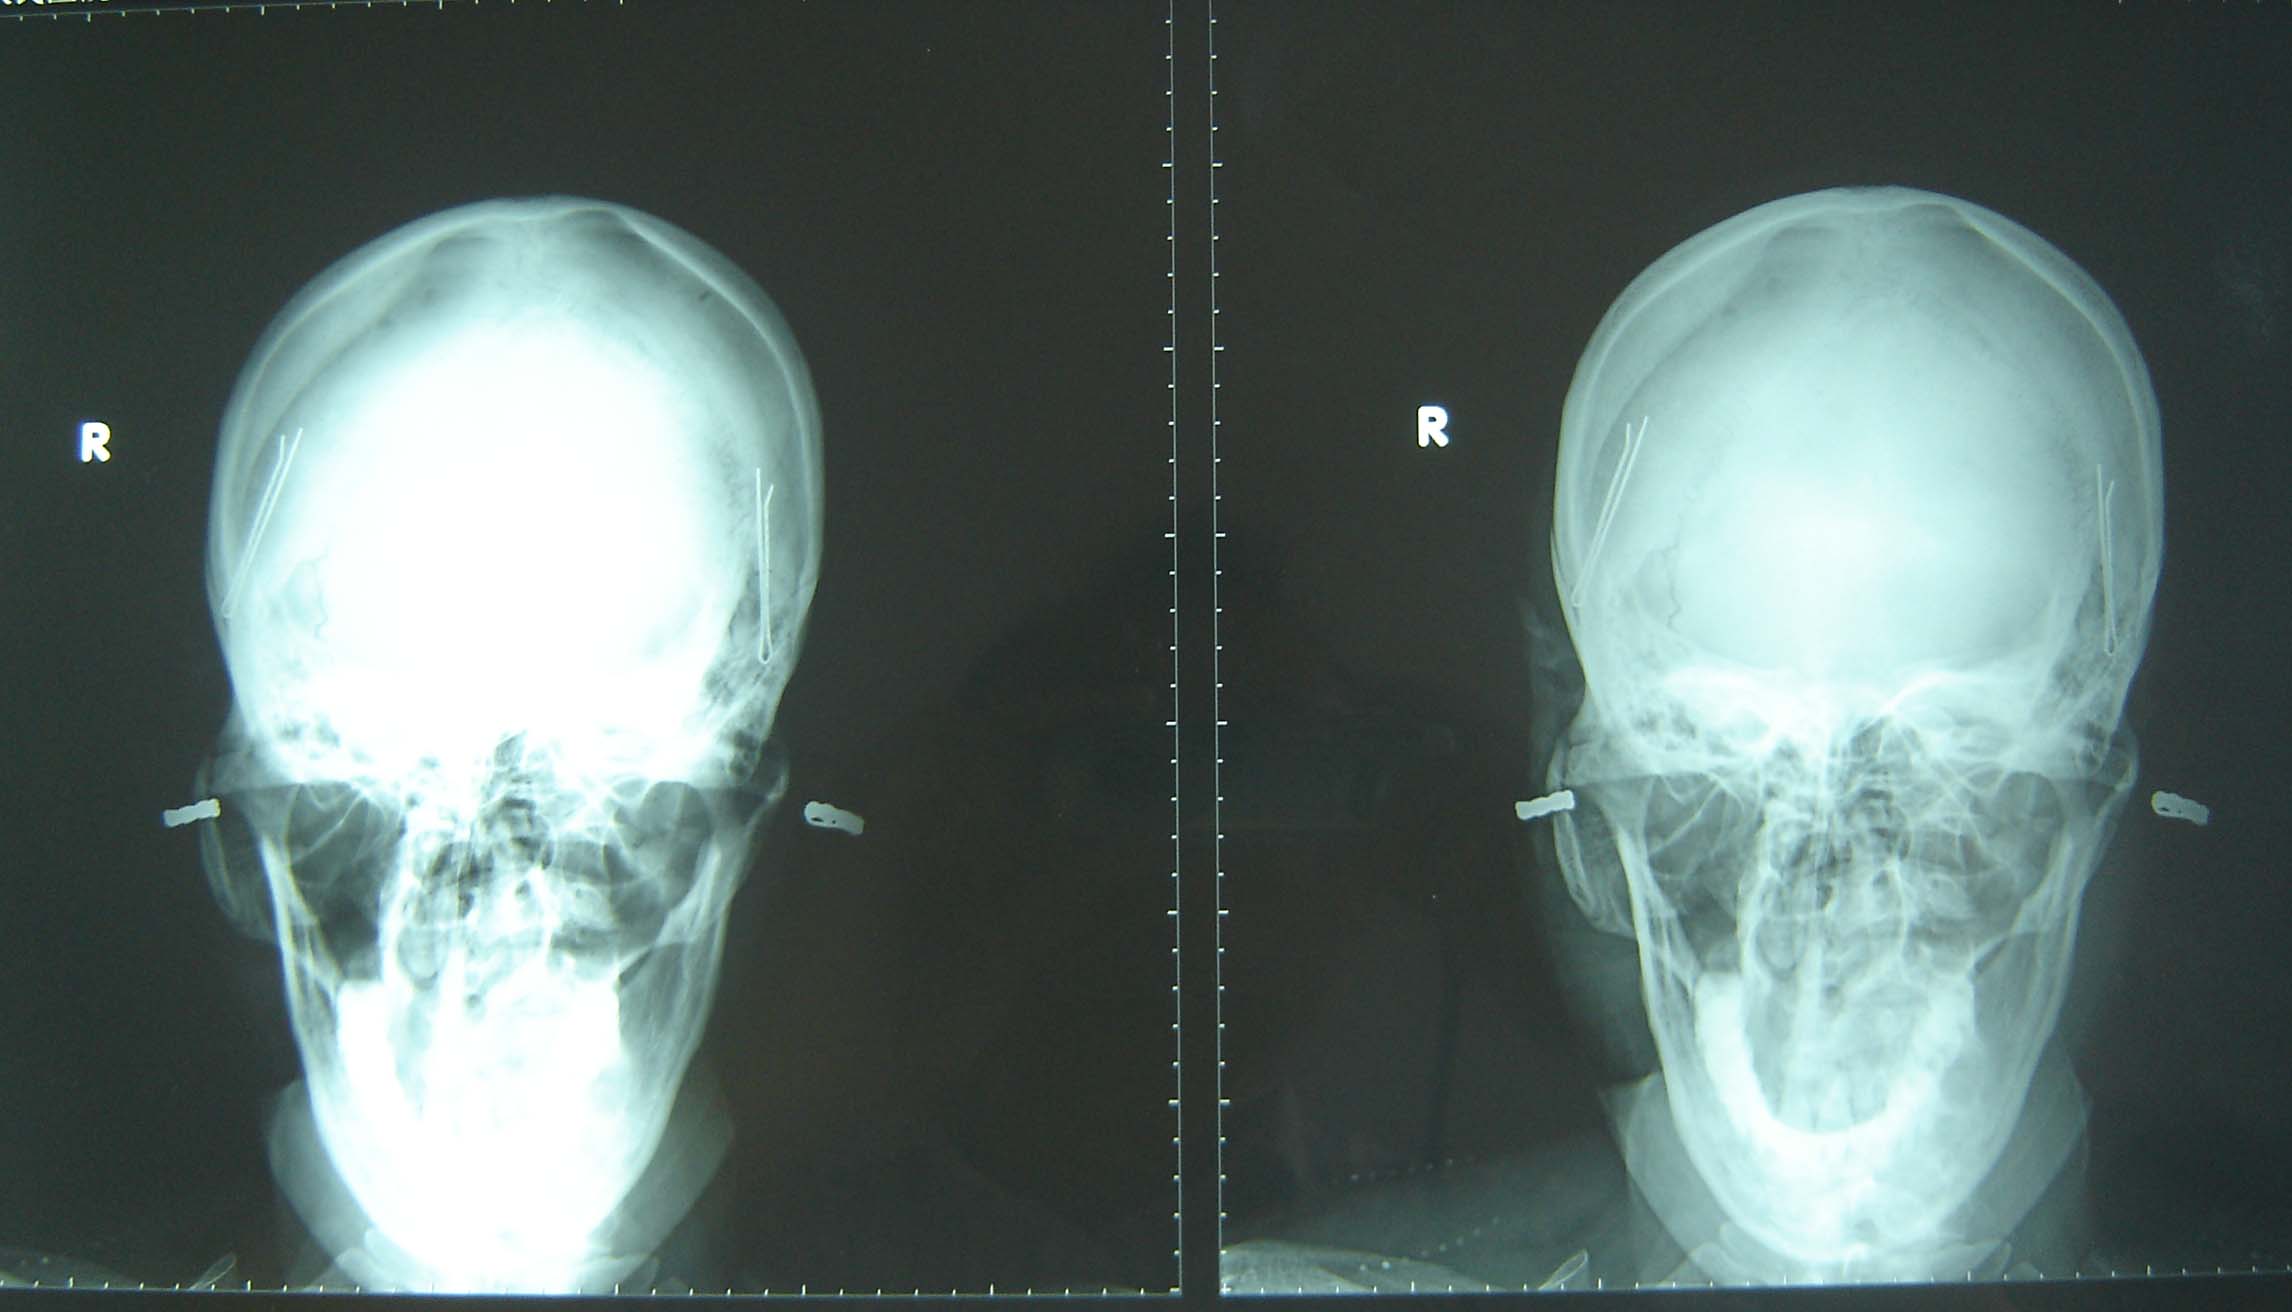

标题: X6268:右茎突过长?

女,46岁,右颈部及咽喉部不适、疼痛半年余,ct、胃镜检查正常。

右茎突不清楚,要专门照茎突片,前后位看不了,正常情况是小于3cm.

看不清,下缘不超过枢椎横突就可以

正位照颈突不清楚,请照颈突标准位